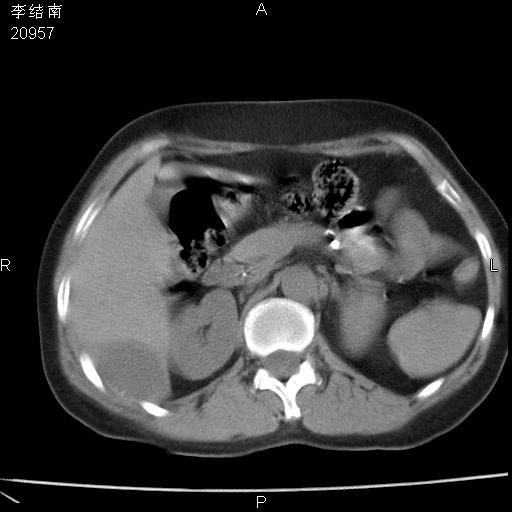

患者女,45岁,以右侧腰部包块来就诊,局部有压痛,皮肤颜色正常。因为是熟人扫的范围较大,患者有胆结石,胆源性胰腺炎病史。请大家看看,有手术病理。

可能大家觉得片子的质量不好,当时是做下腹部扫描,所以没有常规喝水,右腹壁的病灶当时是,密度不均有钙化影,局部骨质没见破坏,肝脏应该是受压的表现,所以当时考虑为腹壁的良性占位,各位老师考虑的神经源性肿瘤,我当时还真没想到,胰腺是胰腺炎治疗后改变.膈脚旁的混杂密度包快不好考虑什么,到上级医院做增强(腹部)+肺部平扫后,发现腹壁的病灶呈不均匀性强化局部可见囊性灶,当时考虑为腹壁结核,最具戏剧性的是膈脚旁的混杂密度灶确是胃的一部分,而腹壁的病灶确是脂肪瘤(简直不可思议)但是我亲眼所见在我们县医院开的.

很不好意思 ,患者后来手术切口裂开,临床医生作了病理证实是腹壁结核。

[病理诊断] CT13183腹壁结核!